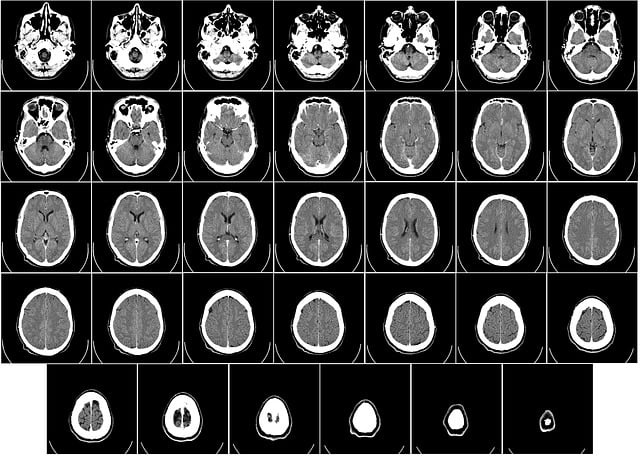

Los hallazgos forman parte de un estudio en el que participaron alrededor de 4.000 personas de hasta 90 años, quienes se sometieron a escáneres que mostraron las conexiones entre sus neuronas.

Estos patrones solo se han revelado ahora gracias a la cantidad de escáneres cerebrales disponibles en el estudio, publicado en la revista Nature Communications.